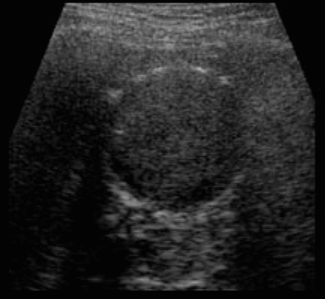

1. Polyp type (용종형)

가장 흔한 타입으로 내부에코가 밝고 균일한 용종모양이다. 또한 조직학적으로 잘 분화된 암이며, 종괴의 크기가 1cm 이상이면 의심할 수 있다.